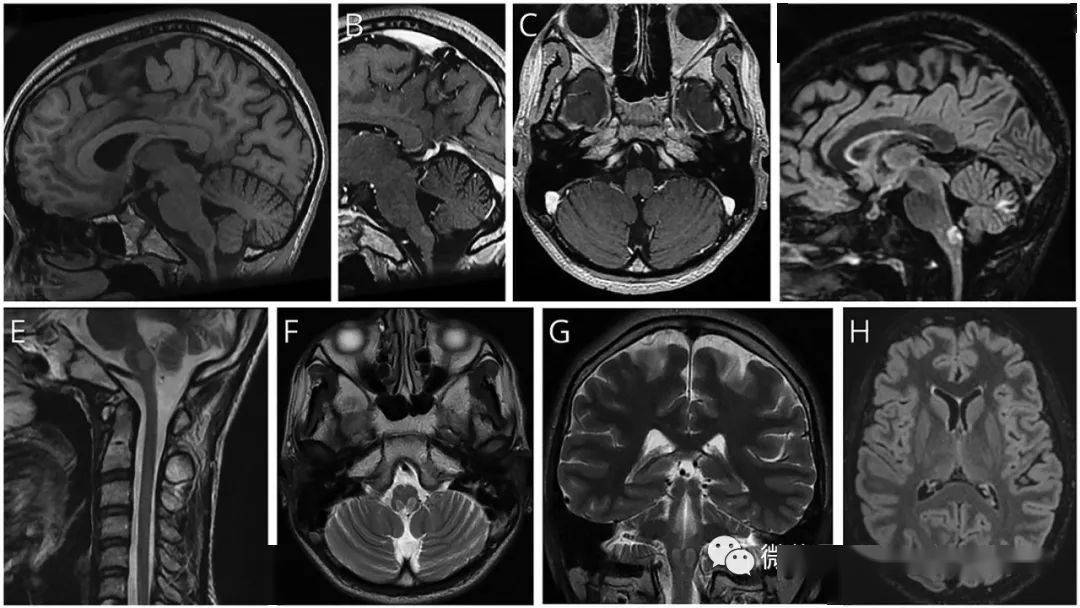

极后区综合征作为亚历山大病的首发表现